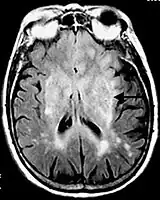

![]() Postcontrast FLAIR of a case of meningitis. It shows enhancement of meninges at the tentorium and in the parietal region, with evidence of dilated ventricles. |

Fluid-attenuated inversion recovery (FLAIR) is an MRI sequence with an inversion recovery set to null fluids. For example, it can be used in brain imaging to suppress cerebrospinal fluid (CSF) effects on the image, so as to bring out the periventricular hyperintense lesions, such as multiple sclerosis (MS) plaques.[1] It was invented by Dr. Graeme Bydder. FLAIR can be used with both three-dimensional imaging (3D FLAIR) or two dimensional imaging (2D FLAIR).

- Meningitis and other leptomeningeal diseases*

* Post-contrast FLAIR images have been added to diagnosis protocol for accurate medical assessment.[2]